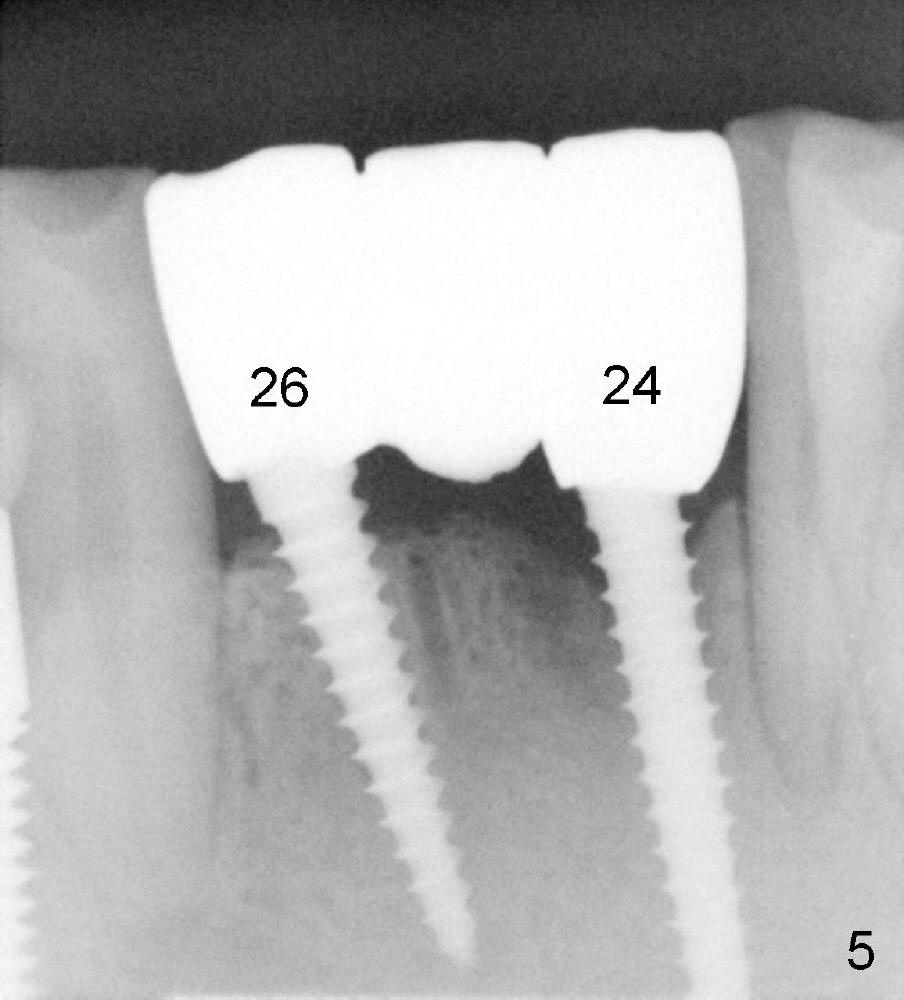

The patient returns for orthodontic treatment 7-8 months post implantation at the sites of #3, 20, 21, and 30 (Fig.4,6,7). He is willing to let the tooth #5 be extracted if necessary, since it has mobility. The tooth is only the functioning posterior tooth in his mouth (Fig.1). It must have occlusal overloading, particularly opposing the implant tooth #28 (Fig.1,7). Multiple implants and ortho treatment appear to be needed.

Clinical exam reveals that the upper midline appears to be deviated to the right (Fig.2), while the left canine relationship is Class II (Fig.3). Therefore, the upper anterior teeth (#9-12) will be moved distally orthodontically. When the tooth #13 is extracted, the immediate implant should be placed more distal than usual. This implant, once osteointegrated, will be used an anchorage for distaliztion of the teeth mesial to it.

Abutments are placed and provisionals are fabricated at #3, 21 and 30 at this appointment. Next visit, bands and brackets will be placed in the lower arch first.